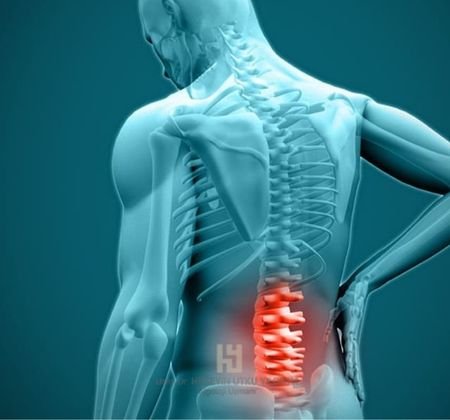

Transforaminal epidural steroid enjeksiyonu, bel ve bacak ağrılarını tedavi etmek için uygulanan modern girişimsel ağrı tedavilerinden biridir. Özellikle bel fıtığı (lomber disk hernisi) ve siyatik nedeniyle sinir köklerine baskı olduğunda etkili sonuçlar verir. Antalya’da Algoloji Uzmanı Dr. Hüseyin Utku Yıldırım, bu tedaviyi güvenle uygulayarak hastalarının ağrılarını azaltmakta ve yaşam kalitesini yükseltmektedir.

Omurga kanalında çıkan sinir kökleri, bel fıtığı veya dar kanal gibi nedenlerle bası altında kalabilir. Bu durum belden bacağa yayılan şiddetli ağrılara yol açar. Transforaminal epidural steroid enjeksiyonu, sinir köklerinin çıktığı foramen adı verilen bölgeye steroid ve lokal anestezik ilaç enjekte edilmesi işlemidir. Bu sayede sinir çevresindeki iltihap azalır, ödem giderilir ve ağrı sinyalleri bloke edilir.